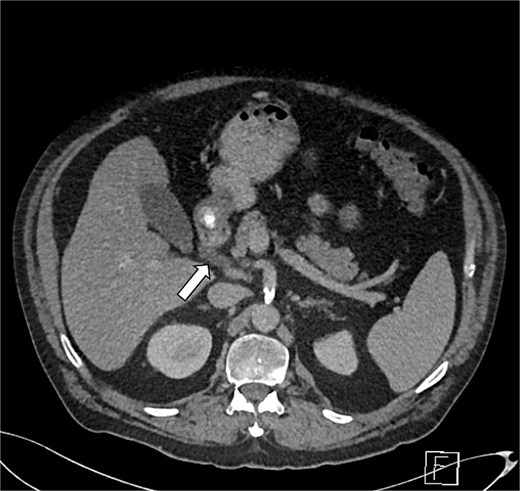

CTAP showed focal inflammatory fat stranding and minor un-encapsulated fluid around and between the second and proximal third parts of the duodenum, with an eccentrically thickened medial wall. The inflammation extended to involve the head and uncinate process of the pancreas (Figs 3 and 4). Acute groove-type pancreatitis is the favored diagnosis given the elevated amylase levels. However, acute duodenitis remains a differential diagnosis. Additionally, mural fat in the caecum and ascending colon was observed, consistent with chronic Crohn’s disease (Fig. 4), and a right-sided fat-containing inguinal hernia was also noted (Fig. 5).

Axial section of abdominal CT scan. The axial section of the abdominal CT scan shows inflammatory fat stranding around the head and uncinate process of the pancreas.

GP was differentiated from pancreatic adenocarcinoma by the presence of a relatively smooth, well-defined inflammatory mass in the pancreaticoduodenal groove, with less aggressive ductal distortion and absence of clear vascular encasement on contrast-enhanced computed tomography (CT). MRCP demonstrated groove-localized inflammation and duodenitis without a focally enhancing mass or typical ‘double-duct’ sign suggestive of pancreatic head malignancy (Figs 1–3).